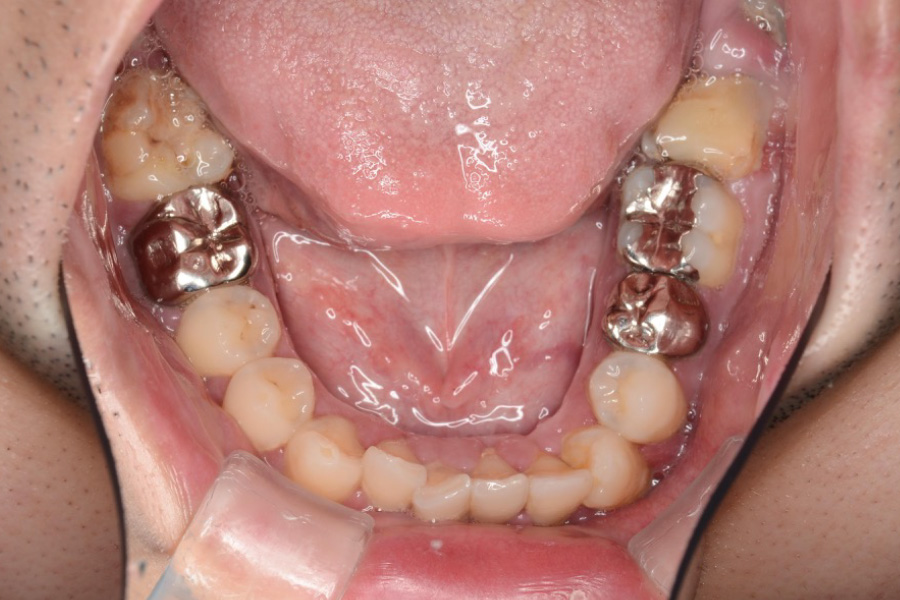

治療前

主訴 上の前歯を揃えたい

治療内容 インビザライン矯正

小臼歯抜歯